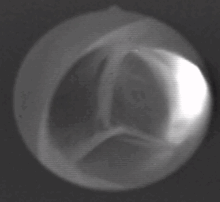

يتكون الصمام من ثلاث شُرَف (باللاتينية: Valvulae) تلتقي معاً على شكل نجمة ثلاثية، تحوي هذه الشرف على مخارج الشريانات التاجية.

يقع الصمام الأبهري عند مخرج البطين الأيسر وعند بداية الشريان الأبهري فيما يسمى بجيب الأبهر، وهو الجزء الأول من الشريان. يتكون الصمام الأبهري من ثلاث شُرَف (أو جيوب) نسيجية وتنبثق عما يسمى بقاعدة القلب أو المستوى الذي تقع فيه باقي صمامات القلب (انظر الصورة).

شُرَف الصمام على شكل جيوب تخرج من حلقة دائرية من النسيج الضام، تلتقي أطرافها الحرة في المنتصف لتشكل حين انغلاقها شكل نجمة ثلاثية (تشبه نجمة المرسيدس)، وتكون أطرافها سميكة لتضمن الانغلاق المتكامل. شُرَف الصمام الأبهري هي:

مقطع عرضي للصمام الأبهري، يُظهر الشرف الثلاث منغلقة، كما يُظهر مخرج الشريان التاجي الأيسر فقط.